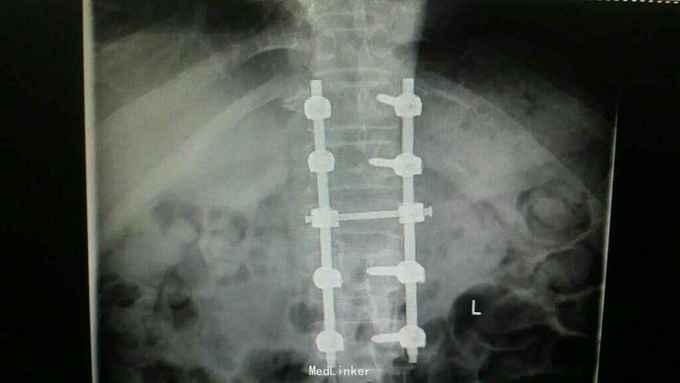

通过影像学,实验室检查,骨髓穿刺检查及行CT引导下穿刺病理结果,患者多发性骨髓瘤诊断已明确。于全麻下行“腰1椎体病理性骨折病变清除减压内固定术”,术中可见病变压迫脊髓明显,彻底减压,术中出血较多,椎体破坏较重,未予骨水泥塑型,术后患者症状缓解明显,拆线后转至血液科进一步治疗。

多发性骨髓瘤是一种单克隆的浆细胞异常增生所致的恶性肿瘤,常以骨骼症状为首发,以脊柱最常累及,本例患者主要手术指征为持续且无法缓解的骨痛,并存在脊髓和神经根压迫症状,,主要影像学表现为穿凿样溶骨性改变,周围无硬化改变。很多全身骨现象无明显的阳性表现,增加了诊断的难度,上面提到的血沉升高,贫血,球白比倒置,血免疫球蛋白升高,骨髓穿刺综合判断,诊断明确后,一般行姑息性手术治疗,一般预后较差,随访见到生存期最长为4年。